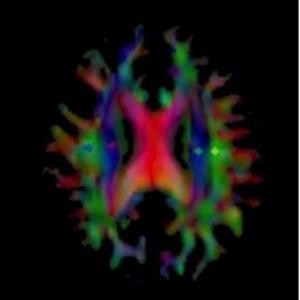

Map of an Alzheimer's patient's brain showing the diffusion of water as part of glymphatic flow

Map of an Alzheimer's patient's brain showing the diffusion of water as part of glymphatic flow...Osaka Metropolitan University